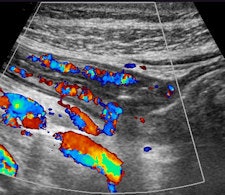

Contrast-enhanced ultrasound (CEUS) is the most sensitive method for detecting even minor blood flow in the bowel, which is a relevant sign for inflammatory bowel disease (IBD). In terms of resolution, CEUS is a more powerful tool than ultrasound alone for characterization of inflammatory masses.

In addition to these technical configurations, the ultrasound equipment must be capable of creating dynamic real-time movie files to show the global perspective of the disease, as well as peristalsis of the bowel. Doppler ultrasound is an essential basic tool as blood flow within the bowel is a possible sign of inflammation.